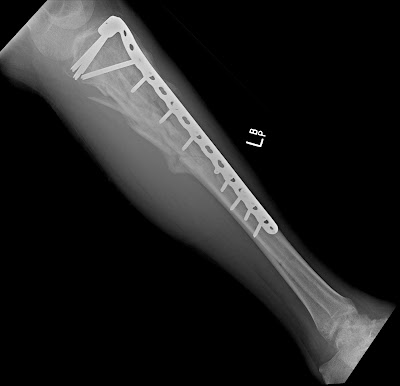

After 10 days, he was returned to the operating room for removal of the fixator and internal fixation with the plate and screws below. A senior orthopedic resident and I spent over 2 hours on this fracture repair with the result below. The fracture through the joint was repaired and the shaft fracture was very well reduced and stabilized. Time will tell if this fracture will go onto complete union. At about 8 weeks out of surgery, the concern is now about whether the fracture will heal before the screws break or pull out of the bone.

Well, it has been 3 months since the initial fracture on Mr. Leg vs. Motorcycle. The latest x-rays are below and seem to show very slow healing. The plan at this time is to return to the OR for a bone grafting.

Films fro August, 2008…